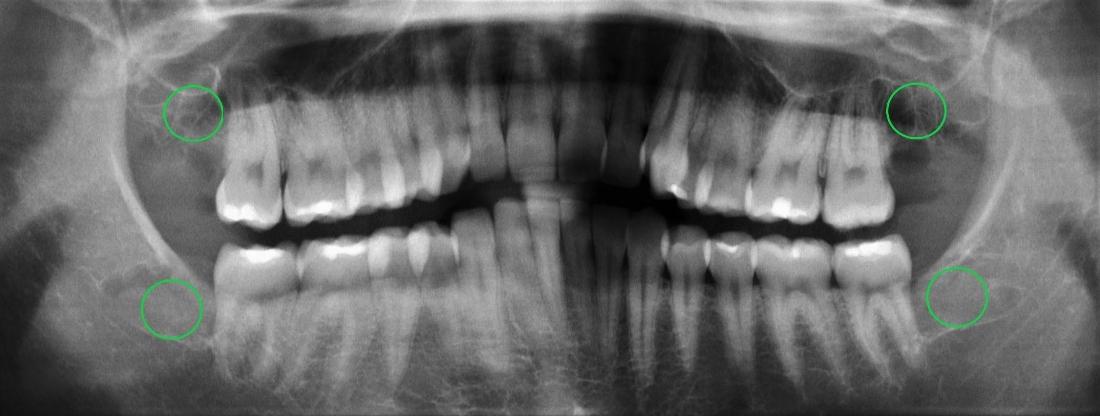

This patient underwent wisdom teeth removal. From discomfort to relief, these before-and-after images highlight how our skilled team ensures a smooth procedure, alleviating pain and safeguarding dental well-being.